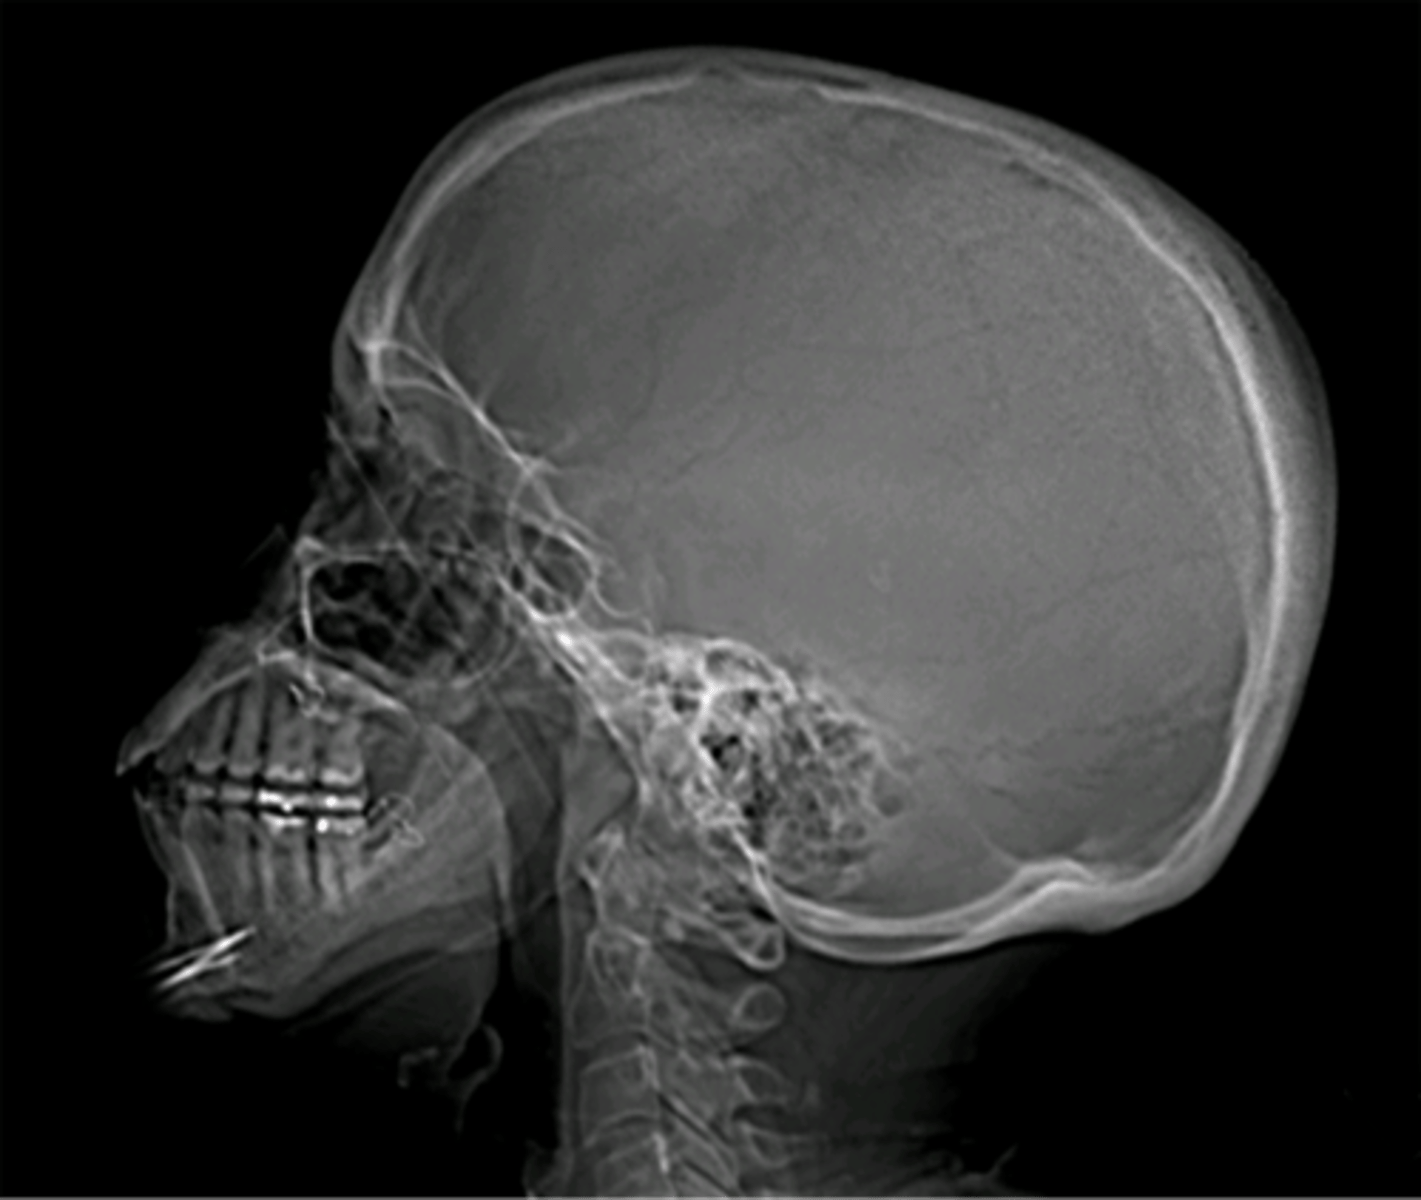

what does this x-ray show

osteoarthritis

something is wrong with the soft tissue